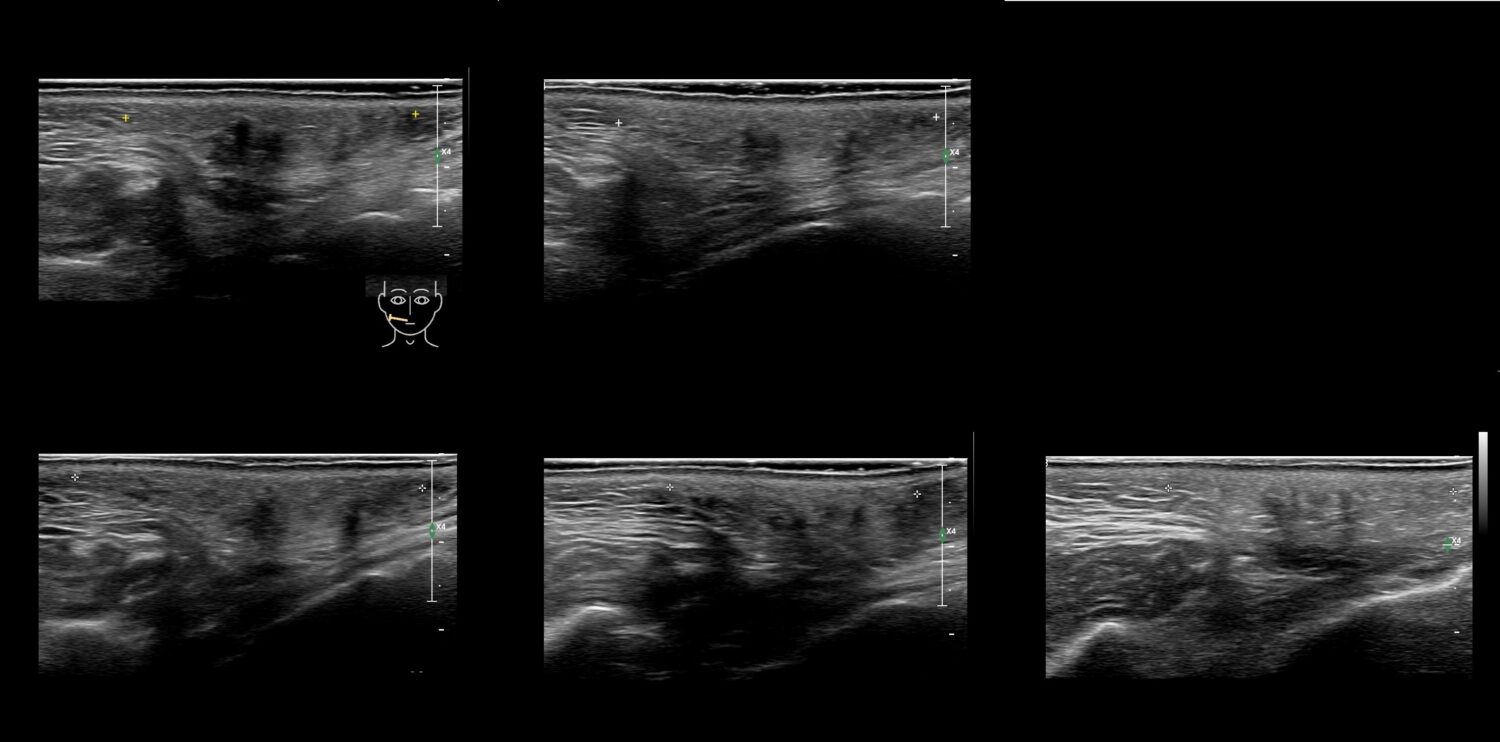

Filler library